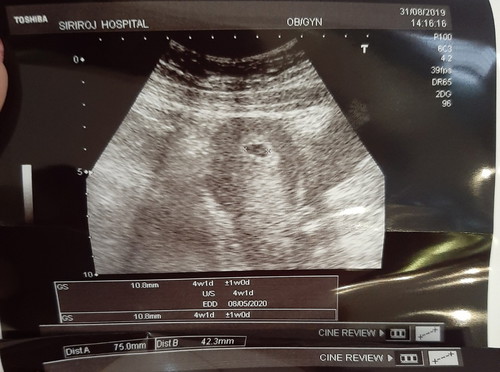

ท้องที่ 2 อายุครรภ์ 4 สัปดาห์ 1 วัน ไปตรวจยืนยันการตั้งครรภ์ คุณหมอซาวหน้าท้องเจอเลยค่ะ แบบนี้คือน้องแข็งแรงมั๊ยคะ ณ ตอนนี้ แม่แพ้ท้องหนักมากค่ะ

4วีค ยังไม่เป็นตัวอ่อนเลยค่ะ รอสัก8-10วีคไปซาวด์ใหม่นะคะ คราวนี้เห็นตัวเล็กชัวร์ค่ะ😊✌️

แบบนี้ สำหรับ 4 วีค ถือว่าปกติจ้า